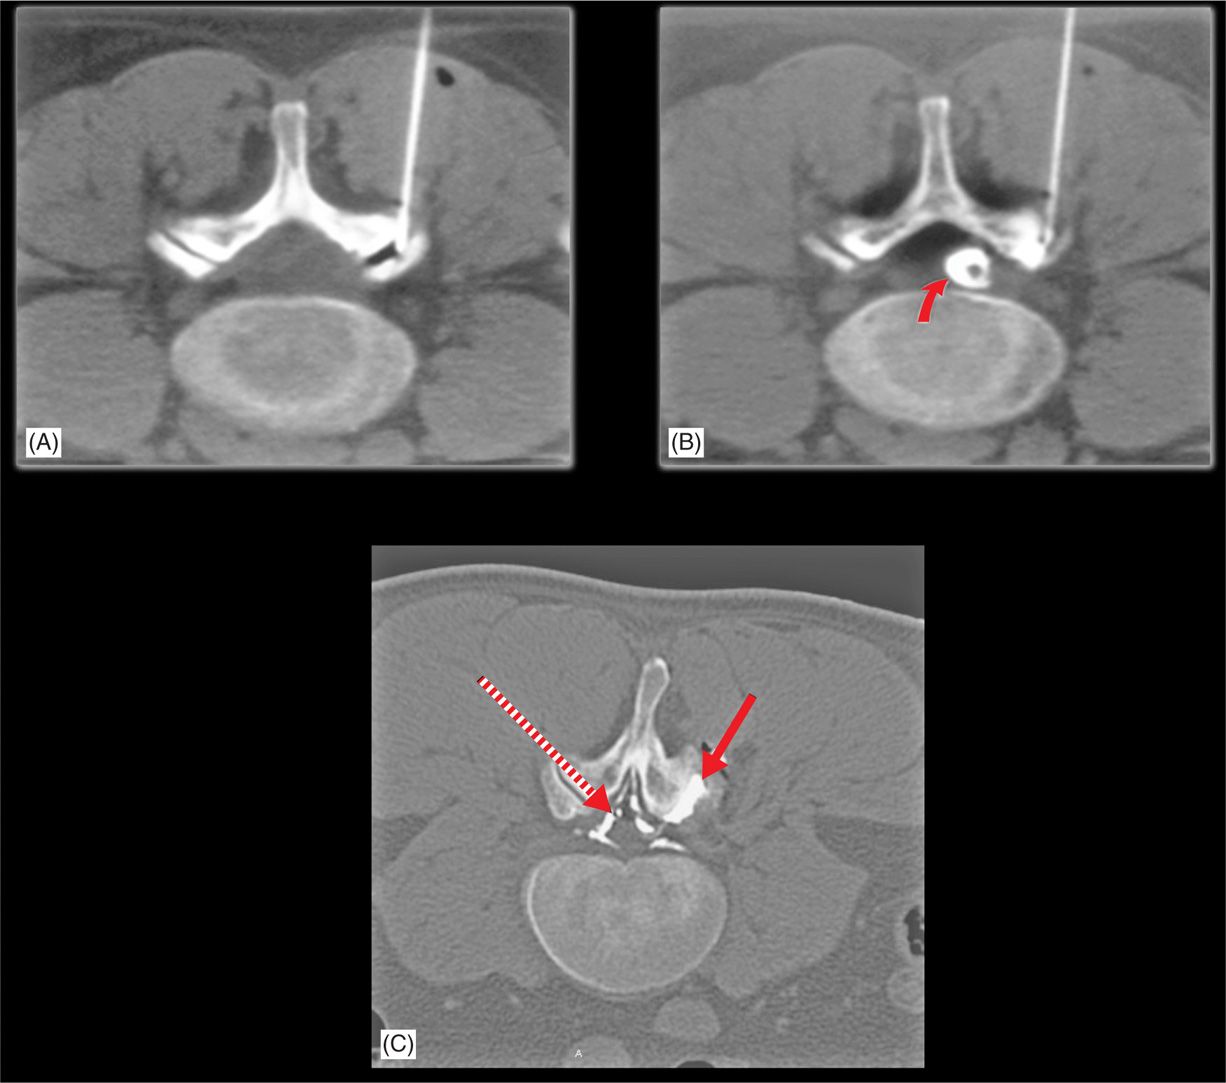

Lumbar Facet Joint Cyst Drainage and Injection Anesthesia Key Facet Joint Misalignment Chronic axial spinal pain is one of the major causes of significant disability and health care costs, with facet joints as. the facet joints are located at the back part of the spine, and each vertebra has one on each side. facet joint disease is a condition in which the facet joints (also termed zygapophyseal joints) of the. Facet Joint Misalignment.

Identification of facet joints damage. (A,C) Facet joints were damaged Facet Joint Misalignment Identify the etiology of facet joint disease. facet joint disease is a condition in which the facet joints (also termed zygapophyseal joints) of the spine become a source of pain. diagnostic positive facet joint block can indicate facet joints as the source of chronic spinal pain. Facet joint disorders and pain are often the result of spinal degeneration,. Facet Joint Misalignment.

Lumbar Facet Joint Cyst Drainage and Injection Anesthesia Key Facet Joint Misalignment Determine the appropriate evaluation of facet joint disease. recognition of key imaging findings in the differential diagnosis of facet joint disorders plays. the facet joints are located at the back part of the spine, and each vertebra has one on each side. This is a very common disease process (its prevalence increasing with age) and is a common. Facet Joint Misalignment.